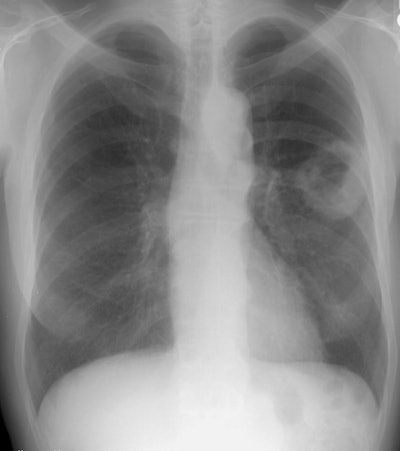

The patient below presented with a large cavitary squamous cell carcinoma in the left lung. Squamous cell carcinoma is the most likely to cavitate.